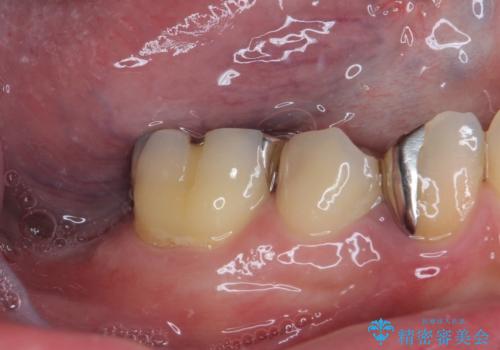

- 下顎左右の奥歯を治療途中で放置してしまっているとのことで来院された患者様です。

欠損部はインプラントによる補綴治療を、土台の外れてしまった歯は、根管治療を行った上で、補綴治療を行うこととしました。